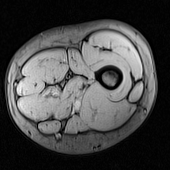

Figure 1: Out-of-phase Dixon MRI scan (a). Image preprocessing results for texture feature extraction (b) to (g). Muscle ground truth (h)

Each volume contained 80 scans of the right thigh (Fig. 1(a)). MRI slice size is 256x256 pixels. To avoid including slices with too few muscle tissue, slices near the knee and the ankle were discarded a priori, resulting in a subset of 40 MRI slices. From this initial selection, 5 consecutive slices were randomly selected from each volume, to simultaneously enable the proposed muscle atlas construction approach and address memory limitations of the experimental setup.

In this paper, the Dalal-Triggs variant was applied, using the VLFeat MATLAB implementation [13], with 16x16 blocks and considering 9 orientations, resulting in a 36 bin histogram. An example of the full HOG representation of a MRI scan is shown in Fig. 1(b).

Obtaining local statistical measures of grayscale images may further provide a description of local texture by describing numerically the local intensity variations. In this research, both the original MRI grayscale image (Fig. 1(a)) and the outcome of a 5x5 LoG filter with σ=1.5𝜎1.5\sigma=1.5 [10] (Fig. 1(c)) are used for statistical feature extraction.